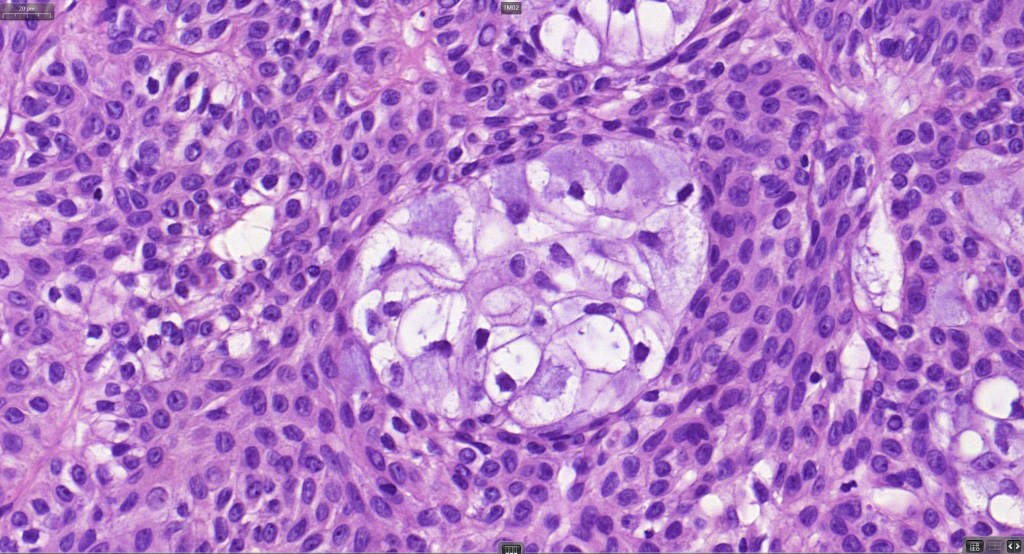

Histological features

•Solid or cystic sharply defined nodule in dermis sometimes extending into subcutaneous fat

•Generally composed of an admixture of small eosinophilic cells & glycogen-rich larger clear cells

•Round to oval vesicular nuclei with small nucleoli or hyperchromatic nuclei

•No pleomorphism & scanty or no mitoses

•Ductal and glandular differentiation

•Squamous differentiation

•Atypical variant- nuclear pleomorphism, hyperchromatism, giant cells & increased mitotic activity (use very sparingly as risk of underdiagnosis of carcinoma is very high!)